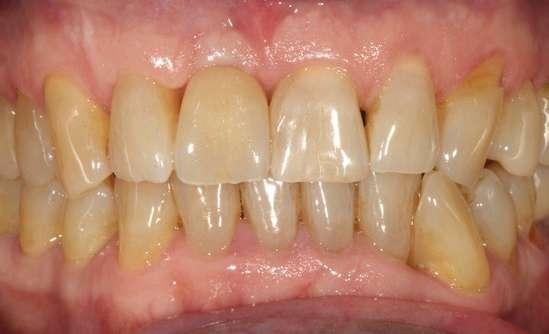

Transcurridos 3 meses desde la cirugía inicial, podemos comenzar a confeccionar la prótesis definitiva que se realiza sobre el mismo transepitelial, para evitar romper las uniones epiteliales formadas a ese nivel y conservar el hermetismo de los tejidos blandos periimplantarios. La prótesis final es una corona E-Max, totalmente cerámica, cementada a una interfase, atornillada al transepitelial unitario. Con esta solución alcanzamos una estética correcta para el

sector antero-superior a la vez de que mantenemos los tejidos blandos periimplantarios sin retracciones, asegurándonos además un correcto ajuste y hermetismo entre la prótesis y el implante (figuras 15-17).

El paciente continúa en seguimiento posterior, con revisiones cada 6 meses durante los dos primeros años. En todas ellas no existe complicación ni pérdida ósea asociada al implante, tal como podemos ver en la radiografía de control a los dos años (figura 18).

Figuras 15 y 16. Imágenes de la corona definitiva colocada en el paciente tras los 6 meses de la inserción del implante y la prótesis de carga inmediata.

Figura 17. Radiografía tras la colocación de la prótesis definitiva.